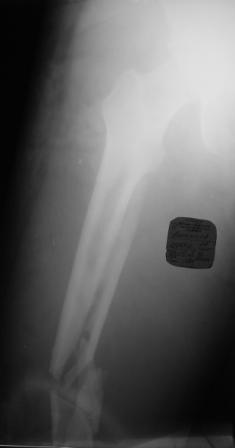

Хотелось узнать Ваше мнение по тактике лечения многооскольчатого перелома бедра

Пациент 26 лет, травма в результате ДТП. Находится на системе скелетного вытяжения. Соматически уже компенсирован. Планируется выполнить остеосинтез бедренной LCP пластиной на тракционном столе, при этом не хотим обнажать зону многооскольчатого перелома. Буду благодарен за критические замечания по предложенной тактике и другие светлые мысли!